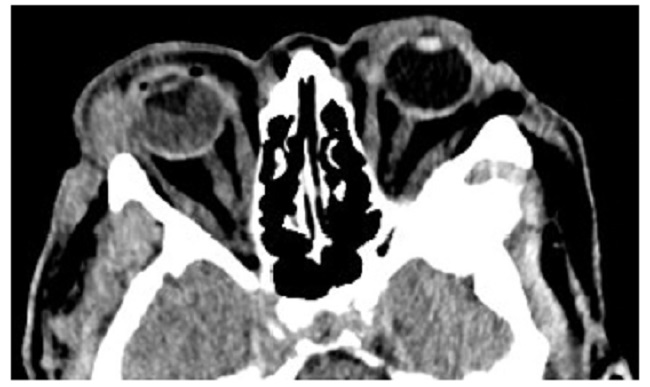

Las calcificaciones oculares y el material médico se pueden confundir con cuerpos extraños u otras lesiones orbitarias1. Las localizaciones típicas de las calcificaciones permiten diferenciarlas de cuerpos extraños hiperdensos. Las más frecuentes son las calcificaciones trocleares, las placas esclerales, las drusas del nervio óptico y la ptisis bulbi. Las primeras tienen localización superomedial dentro de la órbita (Fig. 13), en la tróclea del músculo oblicuo superior, aunque se pueden observar en todas las edades, hay mayor prevalencia de calcificaciones trocleares en pacientes con enfermedades autoinmunes y niveles elevados de fosfatasas alcalinas. Las placas esclerales se localizan en los sitios de inserción de los músculos rectos medial y lateral (Fig. 14) y son más comunes en los pacientes ancianos. Las calcificaciones que ocurren cerca del disco óptico se conocen como drusas del nervio óptico (Fig. 15), las cuales se asocian a degeneración macular y pueden ser causa de pseudopapiledema benigno. La ptisis bulbi es una atrofia y calcificación del globo ocular como secuela de enfermedades infecciosas, inflamatorias o traumáticas previas (Fig. 16) (1,11. Los imitadores de lesiones abiertas del globo ocular incluyen las deformidades como coloboma, estafiloma y el globo ocular elongado por glaucoma o miopía (Fig. 17). Las masas orbitarias y los hematomas también pueden alterar el contorno del globo ocular y asociarse a calcificaciones o relacionarse con desprendimiento de retina (Fig. 18) (1,6,8,11.